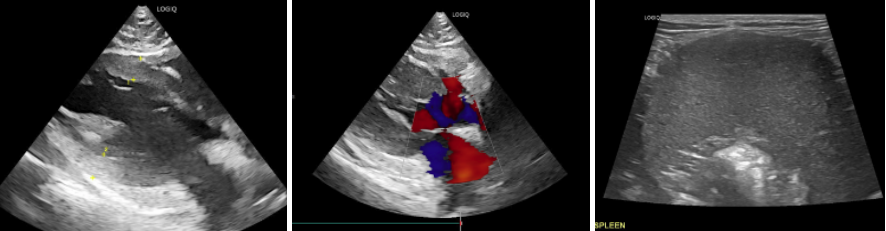

2️⃣ 복부초음파 검사

복부 초음파에서는 비장 비대와 내부 결절 구조가 관찰되었습니다.

비대된 비장과 검사상 확인되는 비만세포종 (초음파검사) / 출처: 에스동물메디컬센터

3️⃣ FNA (세포검사) 진행

복부초음파에서 고양이 비장종양이 의심되어 FAN를 진행하였고, 세포검사에서는 비만세포가 다량 검출되면서 비장 비만세포종양(Splenic Mast Cell Tumor, MCT) 으로 확진되었습니다.

비대된 비장과 검사상 확인되는 비만세포들 (세포검사) / 출처: 에스동물메디컬센터